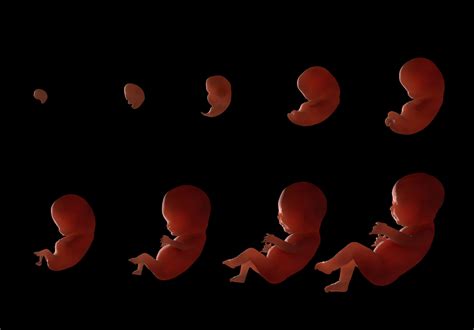

A terhesség egy csodálatos utazás, amely során egy apró sejtből komplex emberi lény fejlődik. Ez a folyamat lenyűgöző változások sorozata, melyet hétről hétre követhetünk nyomon.

A várandósság három szakaszból, azaz trimeszterekből áll. Az első trimeszter a terhesség első 3 hónapját jelöli, ami a 12. hétig tartó időszak.

A terhesség első három hetét visszamenőleg állapítják meg. A terhesség kezdetét az utolsó menzesz első napjától számoljuk. Ebben az időszakban az embrió apró, sejt nagyságú.

A 3-4 hetes embrió körülbelül akkora, mint egy mákszem.

Az 5. hétre a magzat hozzávetőlegesen 9 mm.

A 6-7 hetes embrió már látható.

Mi történik a terhesség 8. hetében? Már magzatnak nevezzük. Mostanra akkora, mint egy málnaszem. A végtagok tovább növekednek. Az arcon kialakul az orrcsont, az orrsövény és az eredetileg széles szájüreg kisebbedik. Málna méretű lettem!

Mi történik a terhesség 9. hetében? A magzat ekkor olívabogyó nagyságú és érzékeli a hangot és a fényt. Az alsó végtagokon még nem, de a felső végtagokon már kifejlődnek az ujjak.

Mi történik a terhesség 10. hetében? A magzat mérete akkora, mint egy szilva, fejlődik az arca, teste egyenesebb alakú lesz s emiatt már kialakul az emberi formája. Na jó, el fogsz ájulni, ha elmondom mit csináltam!

Ezen a fotón már egy 3.6 cm-es, 10-12 hetes magzat látható.

A második trimeszter a 13. héttől a 24. hétig tart. Ebben az időszakban a magzat gyorsan növekszik, és egyre több emberi vonása alakul ki.

A 18. hétre a magzat hozzávetőlegesen 14 cm.

A 20. hétre a magzat hozzávetőlegesen 20 cm.

A 21 hetes magzat pontosan akkora, mint egy banán. A hallás fejlődése a 24. hét környékére fejlődik ki teljesen - tehát már az anyaméhben tökéletesen működik, bár csak tompított formában, ugyanis a picit körülvevő védelmező közeg a hangok egy részét is elnyeli, valamint a füleket és a hallójáratot még magzatmáz borítja.

A harmadik trimeszter a 25. héttől a szülésig tart. Ebben az időszakban a magzat tovább hízik és fejlődik, felkészülve az anyaméhen kívüli életre.

A terhesség vége felé, a 28. és a 32. hét között a pici mintegy másfél kilót hízik!

A 36. hétre a magzat fejlődése szinte teljesen befejeződik. A babák mindössze 5%-a születik a kiírt időpontban, a többség kicsit előbb vagy kicsit később érkezik. Az újszülöttek magzatkori pehely szőrüket elvesztik, a hátukon vagy a homlokukon azonban még találhatunk belőle egy keveset. A szemük kék, ez azonban a következő hetekben még változhat. Az átlagos testsúlyuk születéskor 3.4 kg, hosszuk pedig 50.8 cm.